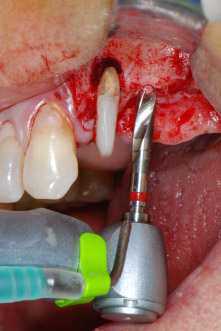

En primer lugar, en un intento por gestionar el problema endo-periodontal, el resto de la superficie radicular se desbridó con cuidado con un equipo piezoeléctrico (Piezomed de W&H, utilizado con el inserto S1 con forma de espátula, concebido en un principio para la erosión de la pared lateral del seno) (figura 4). A continuación, el ápice se erosionó con el mismo instrumento para eliminar el tejido apical infectado residual y reducir las posibles ramificaciones accesorias del canal radicular (apicectomía) (figura 5). No fue necesario realizar un retrorellleno, puesto que la obturación ortógrada se acababa de revisar.

En el siguiente paso, los lechos del implante se prepararon en las posiciones 25 y 26 con instrumentos rotatorios, utilizando un contra-ángulo con un coeficiente de transmisión de 20:1 (WS-75 L, W&H), junto con el nuevo potente motor de implantes Implantmed de W&H (figuras 8 y 19).

La preparación final junto al seno se realizó de nuevo con un inserto piezoeléctrico (Piezomed S2).